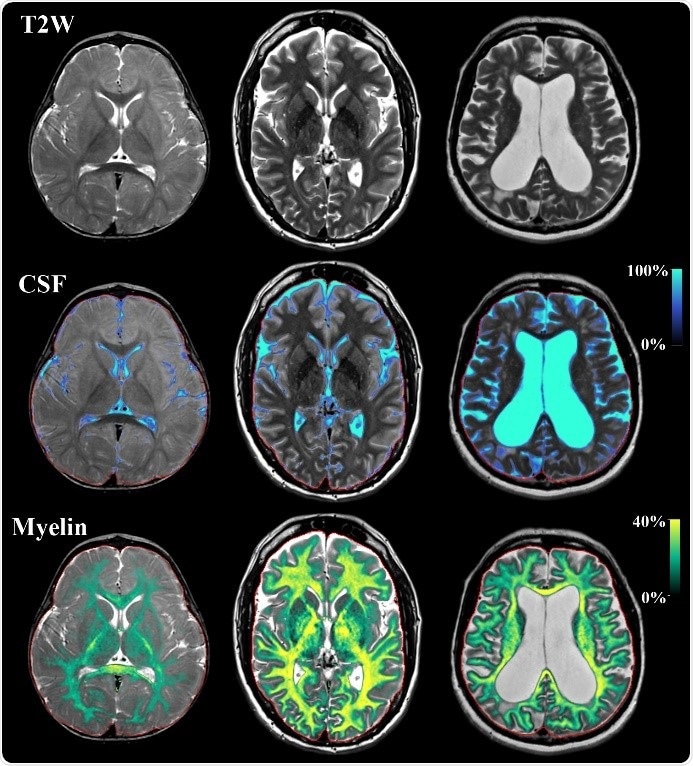

Example of SyMRI imaging on three subjects with the age of 1 year, 43 years and 73 years old. Displayed are synthetic T2-weighted images of an axial slice of the brain. On the same slice a tissue segmentation is performed of cerebrospinal fluid (CSF) and of myelin. Using this map, radiologists can follow signal changes, brain volume and the state of myelination. The acquisition takes 5 minutes for full coverage of the brain.